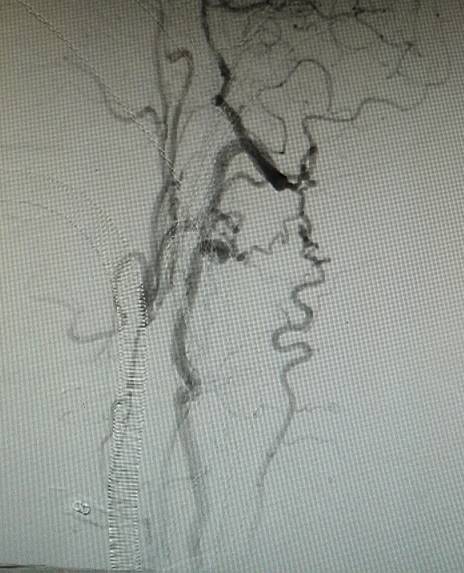

手术过程:全麻后造影示颈内动脉闭塞,经眼动脉从颅外代偿,经前交通动脉自左侧代偿。

经动脉鞘造影,可见远端颈内动脉淡淡显影。

然后球囊扩张,植入支架。植入支架后造影示右侧颈内动脉开通。

术前造影:右侧颈总动脉起始部显影,其余部位闭塞。颈外动脉向颈内动脉代偿供血。

经动脉鞘造影,可见颈总动脉通畅,但管腔狭窄,不规则。

然后球囊扩张,植入颈总动脉支架,造影示,右侧颈总动脉显影好。